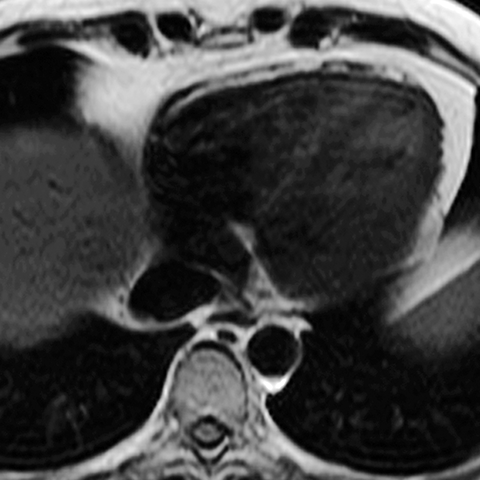

Normal Pericardium (Axial MR) [4 of 8]